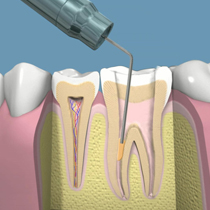

DIENTESIMPLANTES.COM Es una clínica dedicada a la Odontología, Rehabilitación oral e Implantología. Dando así una respuesta a las expectativas de nuestros pacientes.

Contamos con 20 años de experiencia en nuestra labor, lo que nos permite desarrollar procesos integrales en todo el campo de odontología rehabilitación oral e implantología, como consecuencia de ello vemos las expresiones de felicidad de nuestros pacientes al recuperar una sonrisa natural.